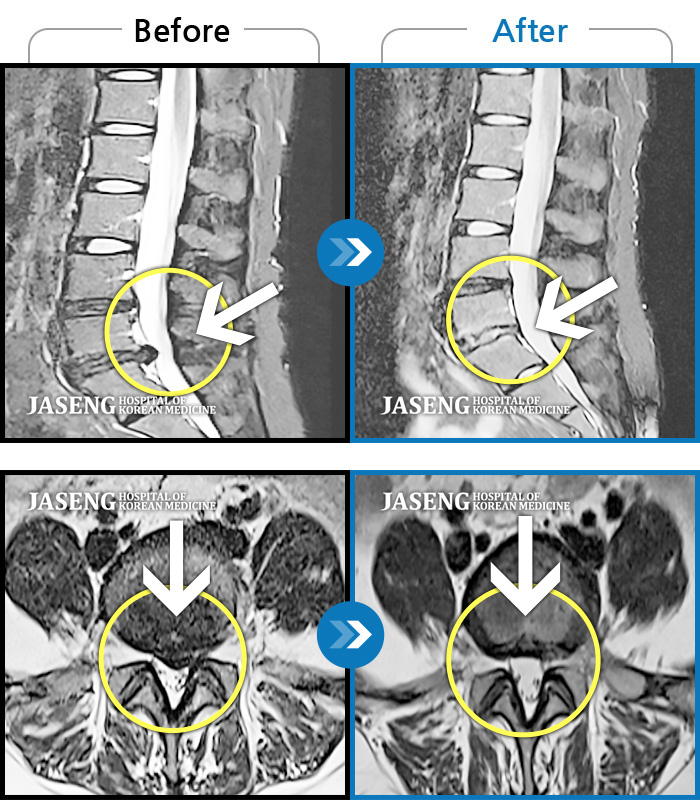

MRI 치료사례

좌측 허리 골반 및 하지 방사통, 야간통